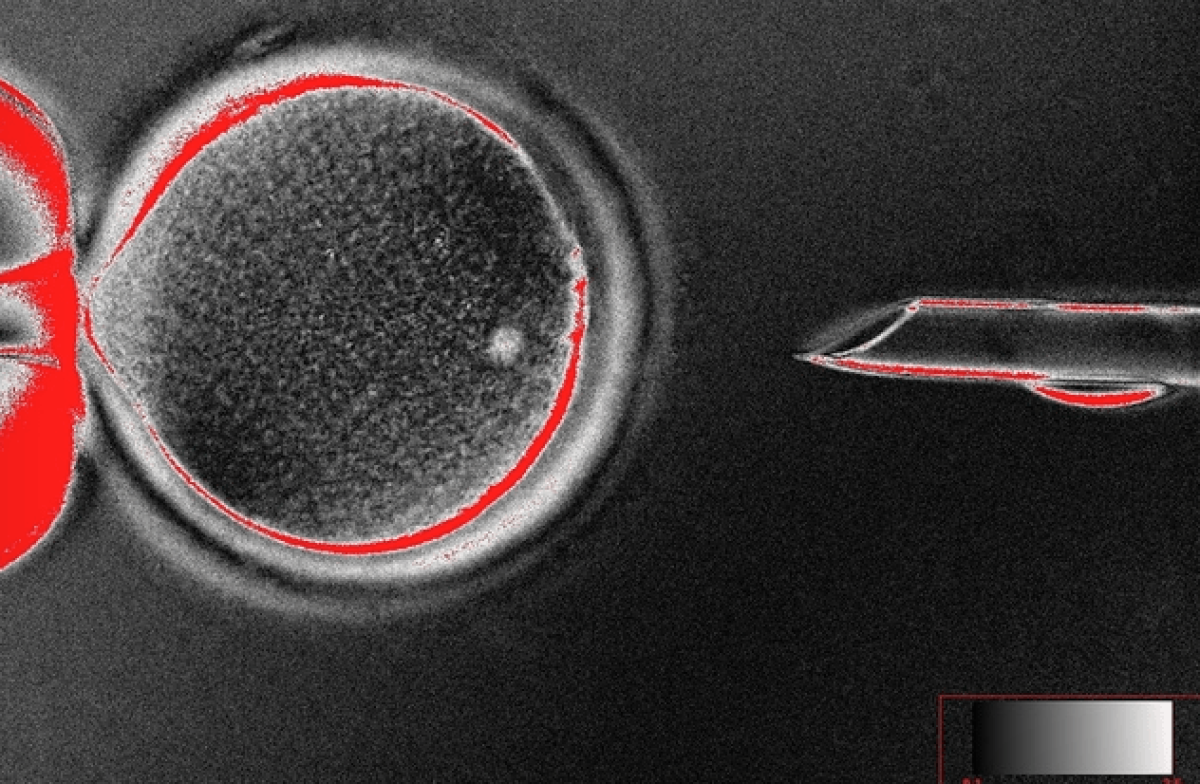

Οι ερευνητές του Oregon Health & Science University με επικεφαλής τον βιολόγο Shoukhrat Mitalipov χρησιμοποίησαν τη μέθοδο μεταφοράς πυρήνα σωματικών κυττάρων, κατά την οποία έλαβαν δερματικά κύτταρα από έναν ενήλικα, αφαίρεσαν από τον πυρήνα τους το τμήμα που περιέχει τη γενετική πληροφορία του (DNA) και το τοποθέτησαν στο ωοκύτταρο μιας δότριας.

Στη συνέχεια με κατάλληλη ηλεκτρική διέγερση και την προσθήκη καφεΐνης ώθησαν τα ωοκύτταρα να αναπτυχθούν σε έμβρυα, τα οποία για πρώτη φορά έφτασαν στο στάδιο της βλαστοκύστης (περίπου 150 κύτταρα ενώ όλες οι πορηγούμενες προσπάθειες δεν ξεπερνούσαν τα 12).